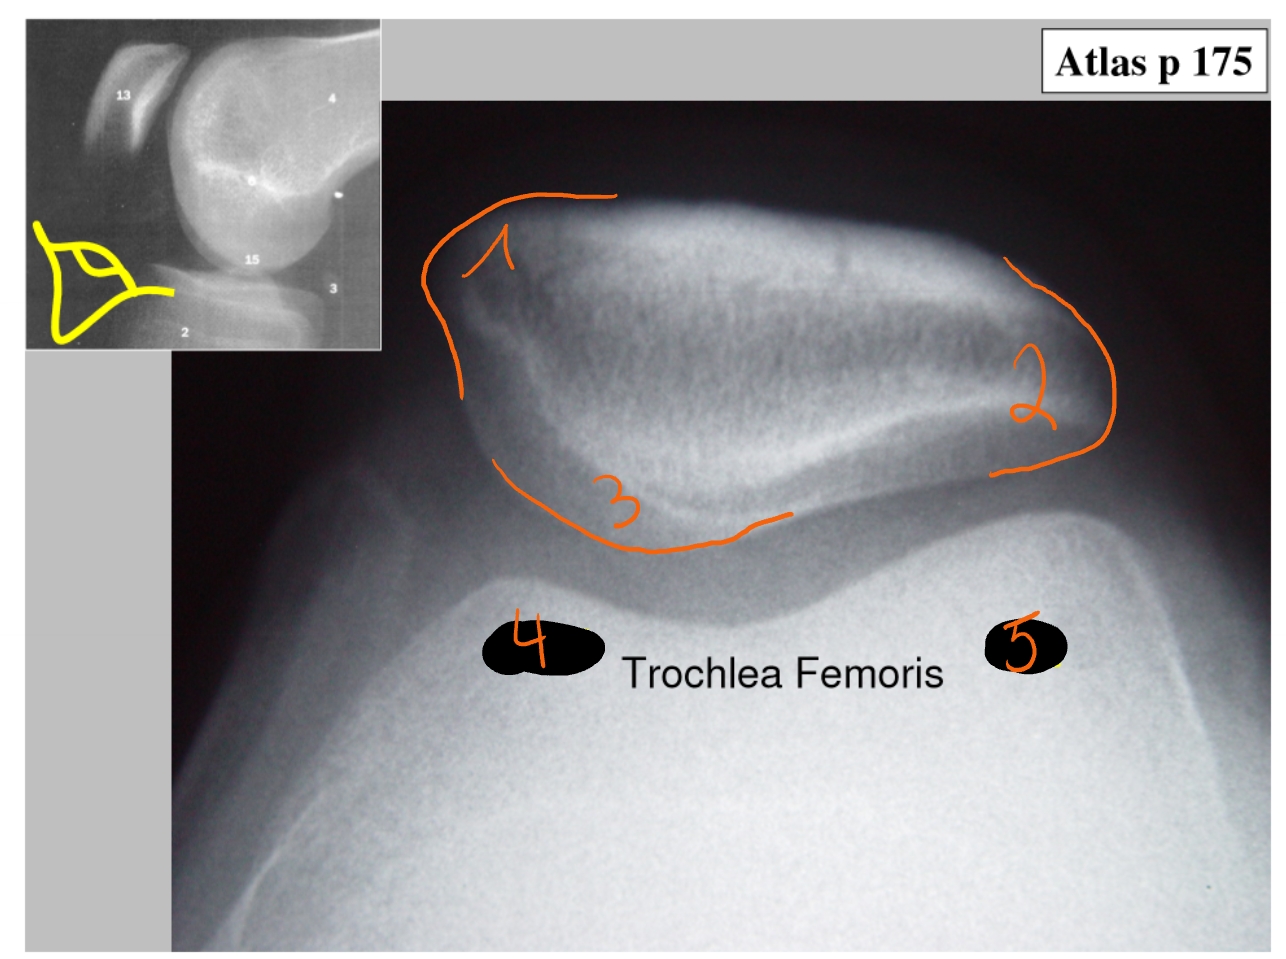

basis patellae

facies articularis van de patella

apex patellae

mediale zijde patellae

laterale zijde patellae

crista

condylus medialis

condylus lateralis

retinaculum = gewrichtsband die patella vasthoudt

= ligamentair

mediale en laterale